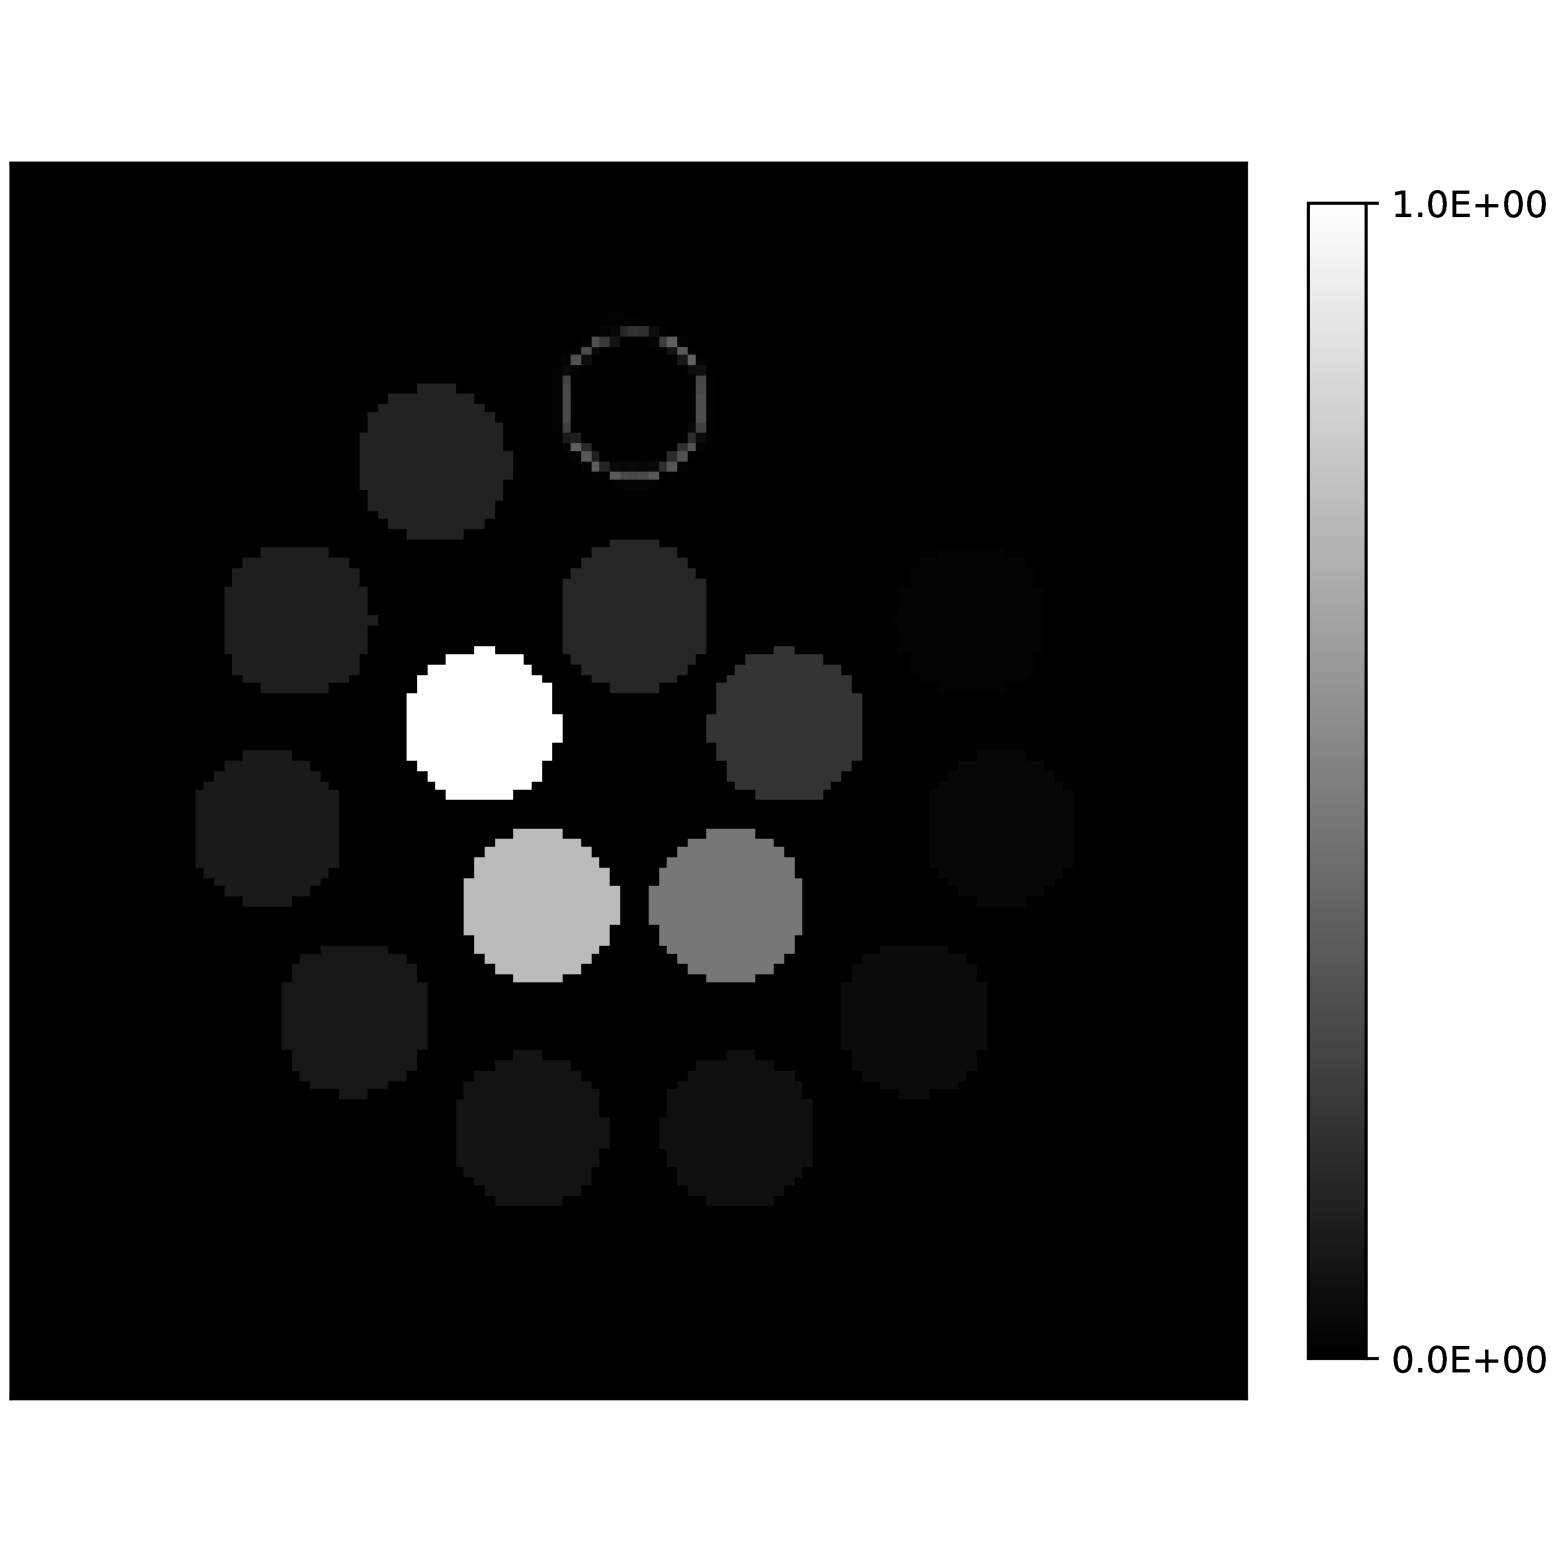

Our theoretical results show that generic concentrations and maps can be recovered exactly even when the fieldmap is not identifiable. To illustrate the impact of this fact, we perform a recovery experiment on a water (Fig. 2(a)), fat (Fig. 2(b)) and silicone (Fig. 2(c)) in silico phantom. The concentrations are all real. The values for the fieldmap and used to generate the signal are shown in Figs. 2(d) and 2(e). The echo times have the form where ms and ms with .

We solve (23) using projected gradient descent as initial iterate a vector with all components equal to one. Forward finite-differences were used to compute the gradient. The bound on the norm of the gradient is Hz at voxels with non-zero signal magnitude, and kHz at voxels with zero signal magnitude. This avoids imposing artificial constraints at voxels with no signal. The step size used is and the termination conditions

In Figs. 2(f), 2(g) and 2(h) show the recovered concentrations of water, fat and silicone, and Fig. 2(j) shows the recovered . These recovered quantities are all qualitatively similar to their true values. In contrast, Fig. 2(i) shows the recovered fieldmap, which differs from its true value. By comparing the errors in the recovered concentrations, we see that they are within a reasonable accuracy except in regions with a large magnitude for the fieldmap gradient, indicating a bound that is too small (Figs. 2(k), 2(l) and 2(m)). A similar behavior is seen in the recovered (Fig. 2(o)). The error for the recovered fieldmap tends to be larger outside the area of the phantom (Fig. 2(n)).